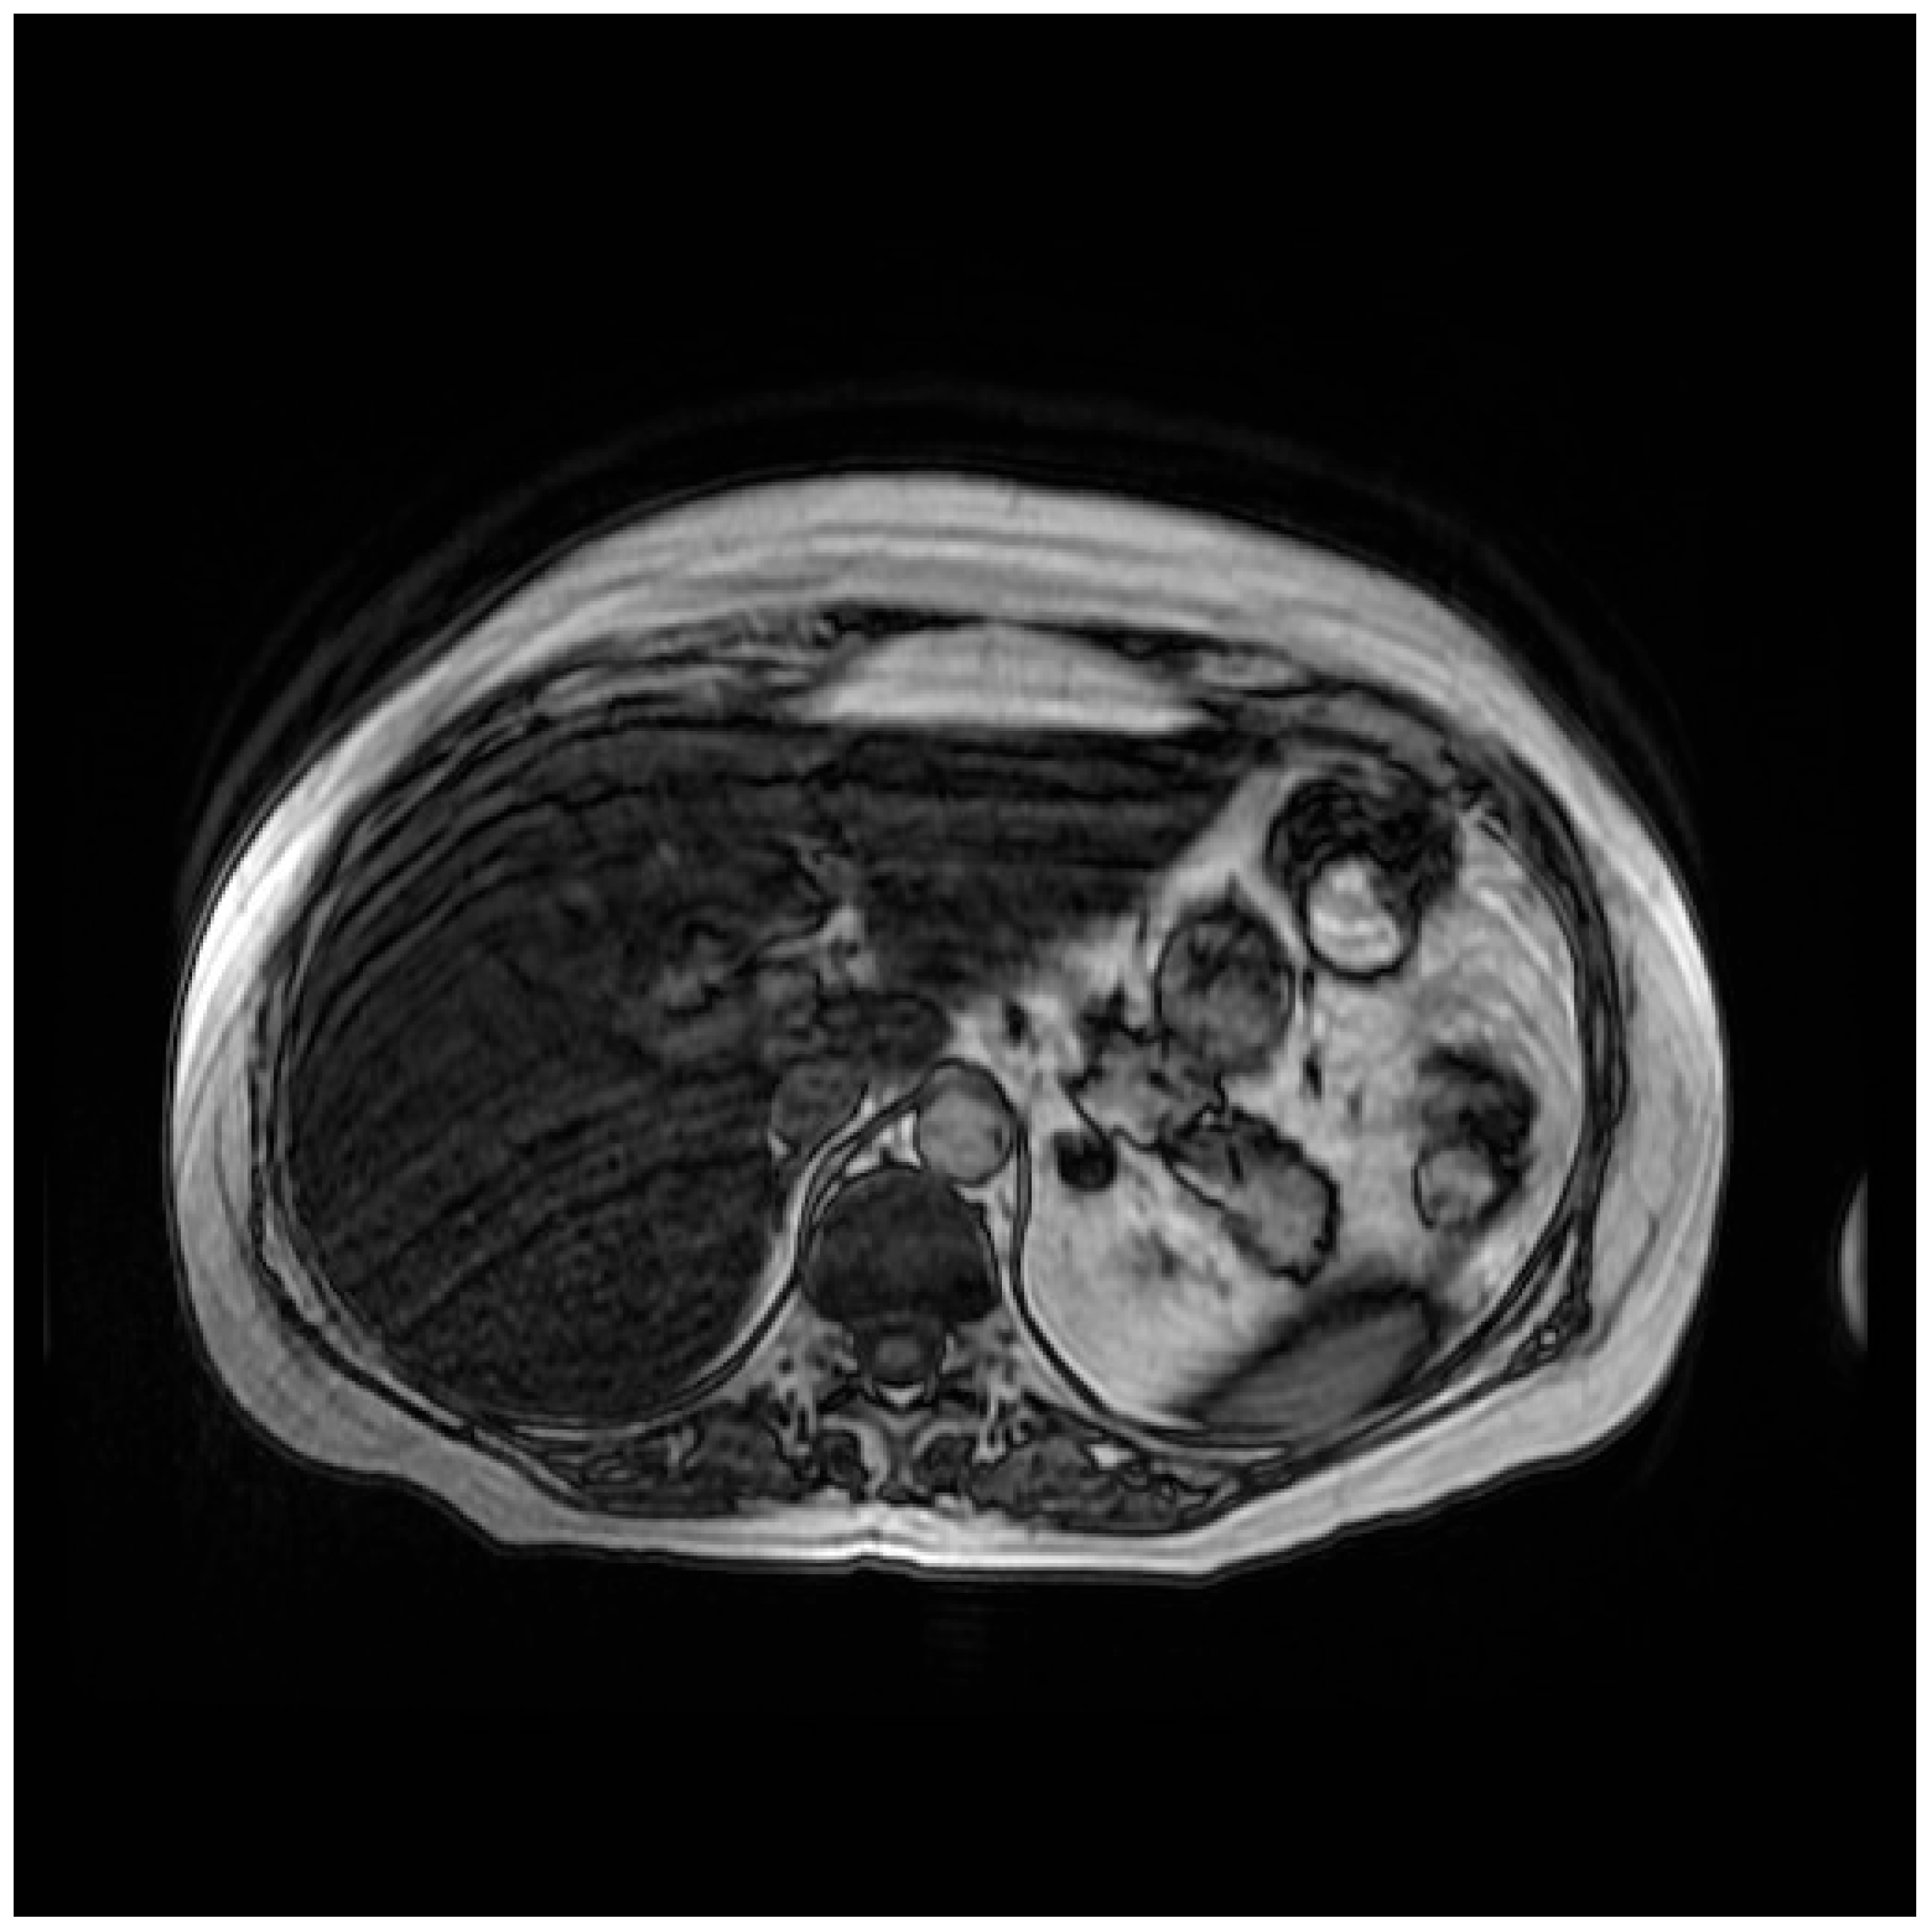

2. Case Presentation